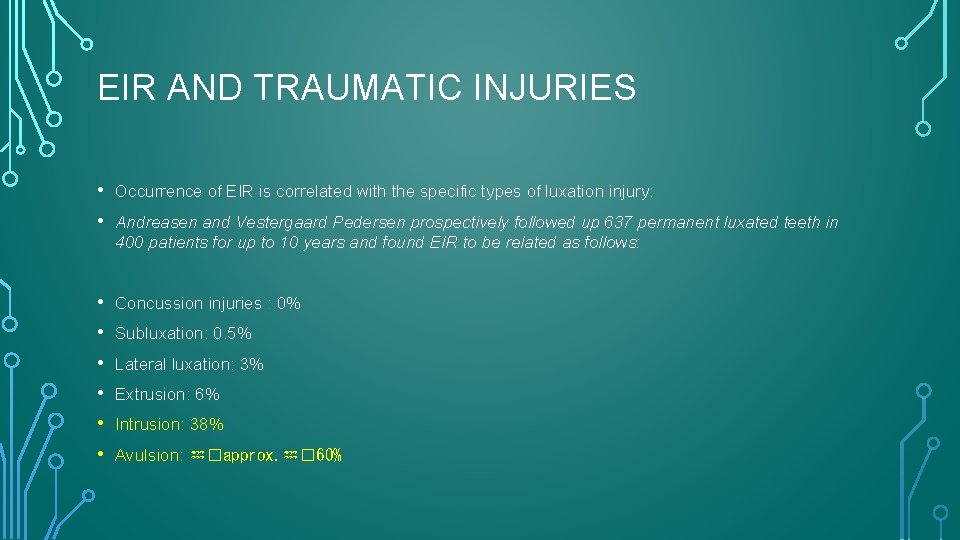

EIR AND TRAUMATIC INJURIES • • Occurrence of EIR is correlated with the specific types of luxation injury: • • • Concussion injuries : 0% Andreasen and Vestergaard Pedersen prospectively followed up 637 permanent luxated teeth in 400 patients for up to 10 years and found EIR to be related as follows: Subluxation: 0. 5% Lateral luxation: 3% Extrusion: 6% Intrusion: 38% Avulsion: ♒�approx. ♒� 60%